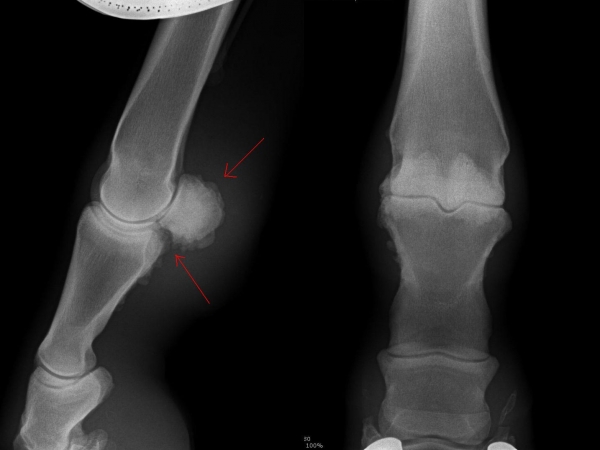

Těžká artróza ve spěnkovém kloubu

Fragment na spěnkové kosti